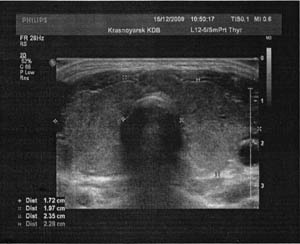

Щитовидная железа. Строение. Заболевания. Методы лечения. |

Метки: Щитовидная железа Строение. Заболевания Методы лечения. |